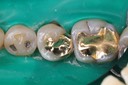

Ted Kanamori #14 prep

Ted Kanamori #14 finish